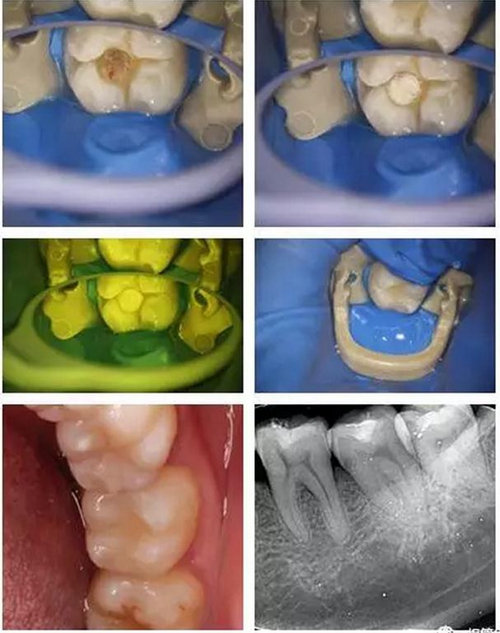

所以當蛀牙的最前沿非常接近牙髓(比如小于0.5mm時)或者已經(jīng)穿通牙髓時,醫(yī)生在顯微鏡下可見透紅或者出血點時,細菌就可能已經(jīng)入侵到牙髓組織,這時即便在我們沒有自覺疼痛癥狀時,保髓的難度和風險就急劇加大了。這時,醫(yī)生需要結(jié)合患者的臨床癥狀、體征以及術中所見等來綜合決定患牙牙髓的保存與否以及如何保髓了。

8.jpg

(這就是一個直接穿髓以后,喻剛醫(yī)生根據(jù)情況決定保髓的成功病例,不過這里要非常感謝現(xiàn)在我們擁有的一些新型的生物材料,大大提高了我們保髓治療的成功率?。?br/>

美學樹脂分層堆塑,還原本真!

10.jpg